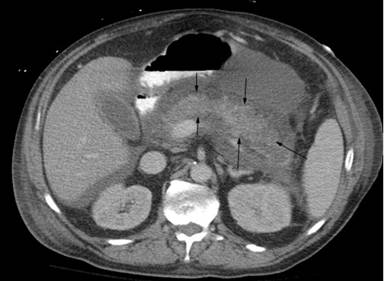

Amylase and lipase levels came down to 100s within 2 days of stopping propofol. Ultrasound of the abdomen showed no gallstones or biliary dilation. CT scan of the abdomen showed an edematous pancreatitis (Figure 1). He had no history of cholelithiasis, cholecystitis, pancreatitis, hypertriglyceridemia or significant alcohol ingestion.

Figure 1. Edematous acute pancreatitis. |